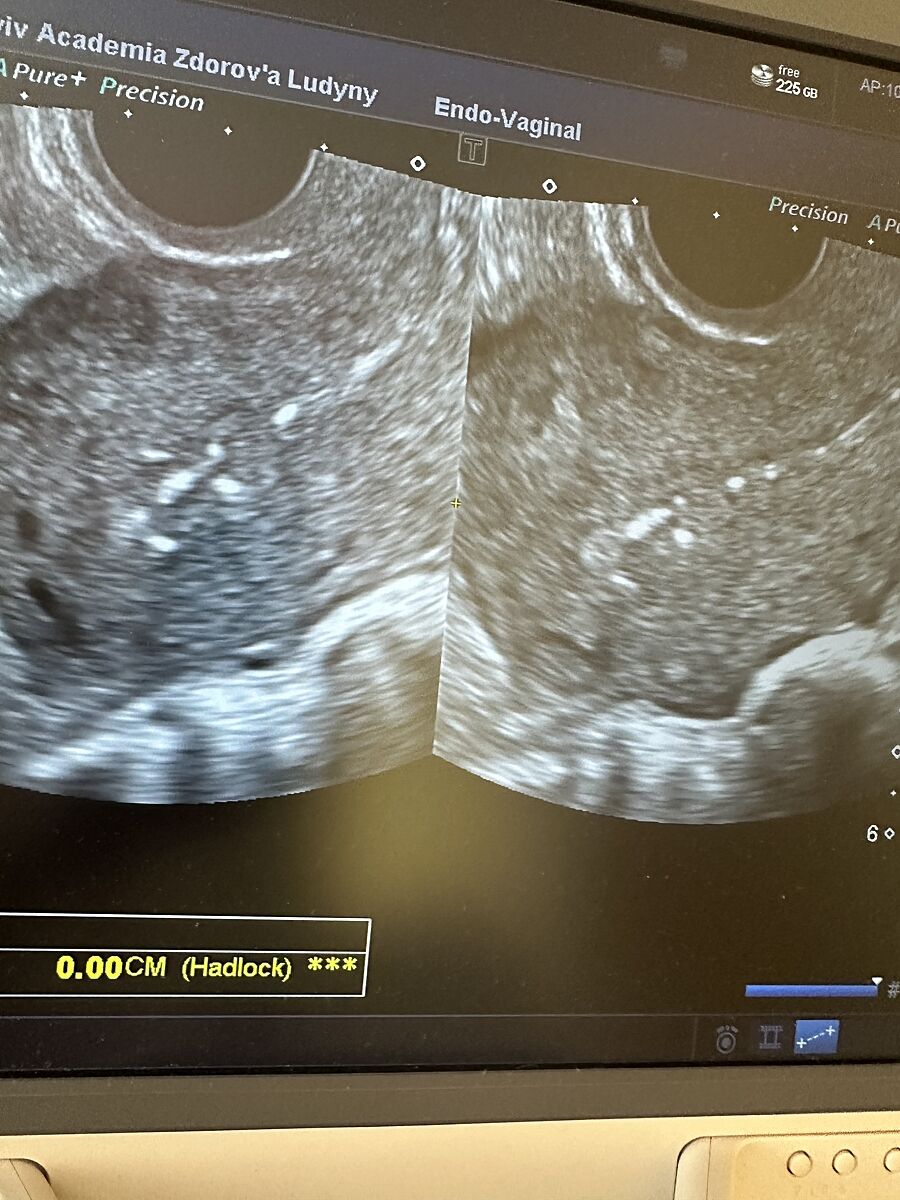

Пошла па узи, в заключение написали Міометрій структура: однорідна.

Порожнина матки: розширена до 9мм, за рахунок гетерогенного утворення з

лінійними включеннями, кровоток не візуалізується